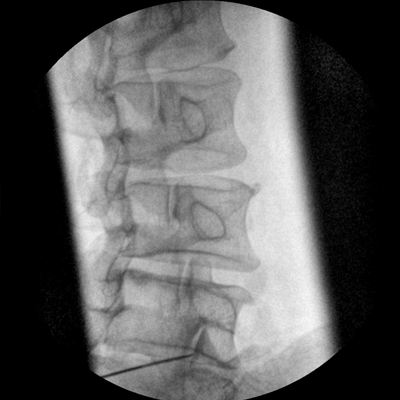

專業(yè)的圖像處理系統(tǒng),為您提供高分辨率、高灰階圖像。